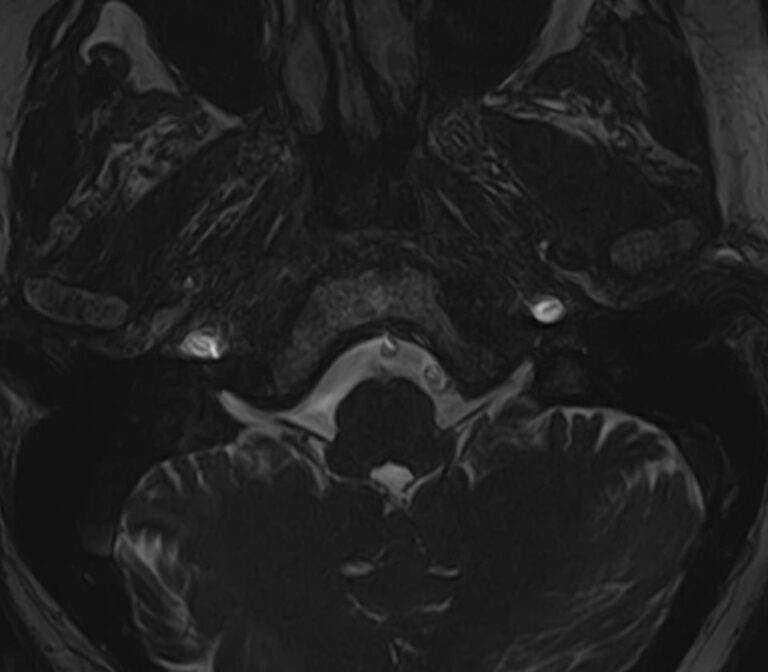

Мосто-мозжечковый угол — это пространство вблизи основания черепа в виде углубления между анатомическими образованиями: продолговатым мозгом, мозжечком и Варолиевым мостом. В этой области располагаются волокна многих черепно-мозговых нервов (например, лицевого, тройничного, преддверно-улиткового), проходят мозговые артерии и многочисленные вены мозжечка.

В мосто-мозжечковом угле часто развиваются воспалительные процессы (арахноидиты) с формированием в дальнейшем арахноидальных кист. Могут выявляться аневризмы расположенных здесь артерий. Но чаще всего в этой области образуются объемные образования, как злокачественные, так и доброкачественные, которые сдавливают расположенные там нервные волокна, кровеносные сосуды и пути ликворного оттока. Наиболее часто встречающаяся опухоль этой области — невринома преддверно-улиткового нерва. В большинстве случаев она имеет доброкачественный характер, развивается, как правило, у людей трудоспособного возраста, преимущественно у женщин. Реже встречаются менингиомы и холестеатомы мосто-мозжечкового угла.

Самым информативным, при этом быстрым и безопасным, методом диагностики опухолей мосто-мозжечкового угла на сегодняшний день является магнитно-резонансная томография с контрастированием. В клинике «Доступная медицина» проводится эффективная диагностика патологии мосто-мозжечкового угла с использованием новейшего томографа TOSHIBA VANTAGE TITAN 1,5 Тесла. Высокая мощность магнитного поля 1,5 Тесла позволяет получить подробное изображение этой труднодоступной для диагностики области в различных плоскостях.

Контрастирование проводится контрастным веществом на основе солей гадолиния (химический элемент, относящийся к редкоземельным металлам). Применяемый контрастный препарат накапливается в патологическом очаге, за счет чего при сканировании усиливается его яркость изображения. Это дает возможность выявить опухоли малых размеров (до 3 мм) и назначить своевременное лечение. Кроме того, контраст заполняет просвет сосудов, благодаря чему на снимках появляется детальное изображение сосудистой сети. Это позволяет диагностировать патологическую извитость, аневризмы, мальформации, при вазоневральном конфликте — зоны сдавления черепно-мозгового нерва кровеносным сосудом.